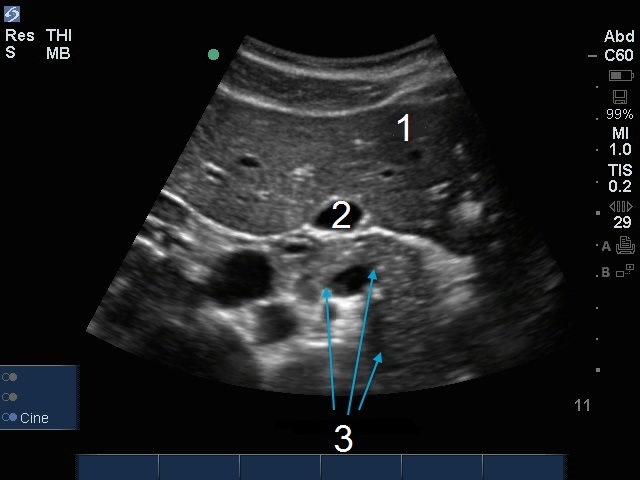

Imagen de la vesícula biliar y páncreas

Hígado

Ves. Biliar (VB)

Transversal del páncreas